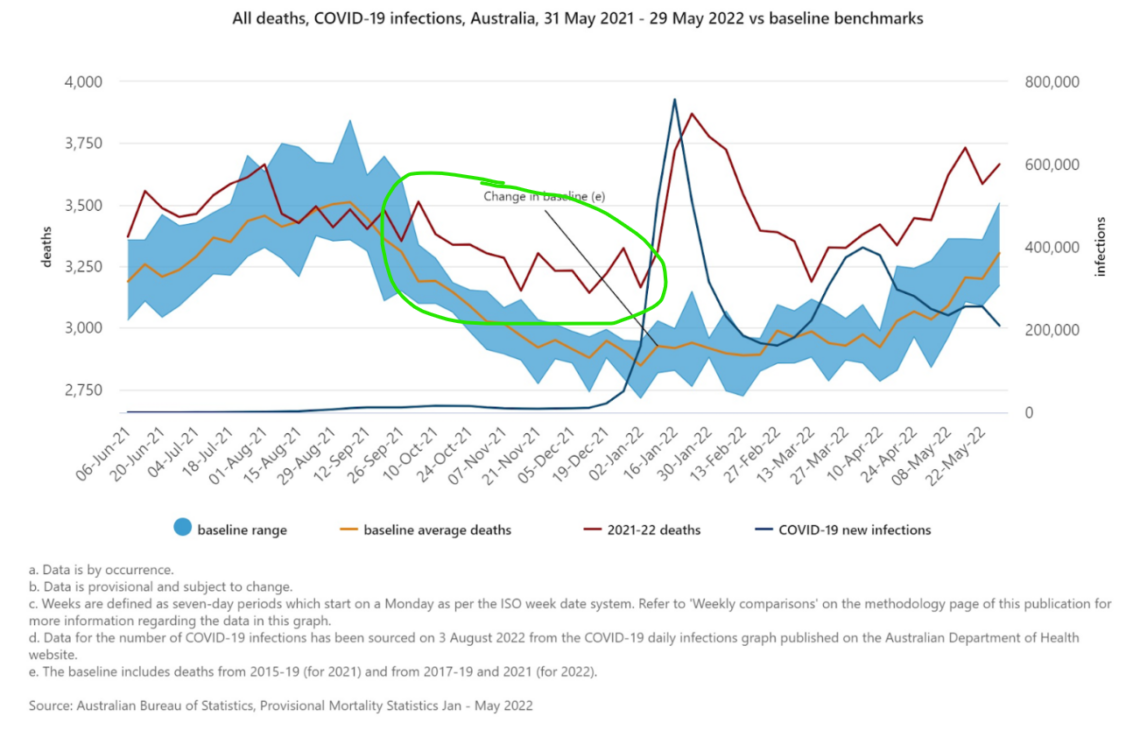

In Australia, there was 1,303 excess deaths in 2020, during the “worst pandemic in 100 years.” Strangely enough, Australia’s excess deaths jumped by 747 percent in 2021, when a “lifesaving” vaccine had already been rolled out. The 11,042 excess deaths in 2021 made the pandemic of 2020 seem trivial in comparison. Even worse, by the end of July 2022, Australia recorded more excess death in seven months than the previous two years combined. The country suffered from 18,973 excess deaths in the first seven months of 2022!

According to the OECD database, there were over 1 million excess deaths between Jan 1, 2021 and week 40 of 2022 in the United States alone. According to EuroMOMO, there were 690,000 excess deaths across 28 European countries, beginning in 2021 and ending week 46 of 2022. When these excess deaths are combined Canada’s 54,176 excess deaths and Australia and New Zealand’s 36,710 excess deaths, that’s at least 1.8 million excess deaths in a little over a year and a half!

Prior to the shots being unleashed under Operation Warp Speed, there were very few actual COVID infections in Australia, which the Health Advisory and Recovery Team (HART) pointed to as the world’s “control group” when it comes to exposing the jabs as the culprit in serious injuries and deaths.

Before the shots’ release, Aussies were doing just fine. After the shots’ release, however, people started to get sick with what the establishment had dubbed as “COVID,” even though the COVID jabs are clearly the culprit.

Australia “did not have prior COVID as a reason for seeing this rise in mortality and hospital pressure from spring 2021,” HART noted, adding that “the results from this control group indicate that the cause of this rise in deaths, particularly in young people, must be something in common with Australia, Europe and the USA.”